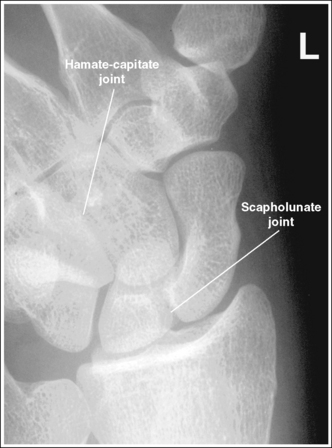

The scaphocapitate and scapholunate joints are open. The ulnar styloid is in profile medially.

• The scaphocapitate and scapholunate joints are open when the wrist is medially rotated approximately 25 degrees. This obliquity is accomplished somewhat naturally as the patient's wrist is ulnar-deviated, with the humerus abducted and positioned parallel with the IR, and the elbow placed in a flexed lateral projection. If the scaphocapitate joint space is closed and the capitate and hamate are demonstrated without superimposition, the degree of obliquity was insufficient (see Image 58). If the scapholunate joint space is closed and the capitate and hamate demonstrate some degree of superimposition, the wrist was rotated more than needed (see Image 59). Excessive external wrist obliquity often occurs when the humerus and forearm are not positioned on the same horizontal plane and the elbow is not placed in a lateral projection. On a PA axial projection, one can judge accurate humerus, forearm, and elbow positioning by evaluating the ulnar styloid. Accurate positioning places the ulnar styloid in profile medially. If the arm is not positioned accurately, the ulnar styloid is demonstrated distal to the midline of the ulnar head (see Image 60).

The scaphocapitate joint is closed and the hamate-capitate joint is open. The wrist was not externally rotated enough.

The scapholunate and hamate-capitate joints are closed. The wrist was externally rotated more than needed.